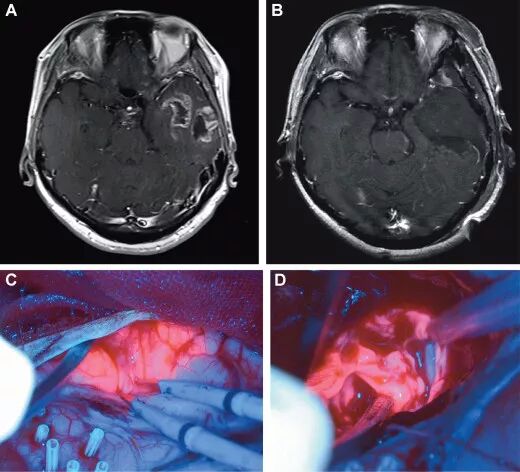

![]()

图4. A.60岁女性患者,左侧颞叶胶质瘤术前MRI增强成像;B.术后MRI增强成像;C.荧光图像清晰显示颞叶表面肿瘤边缘;D.深部白质离断时的图像。